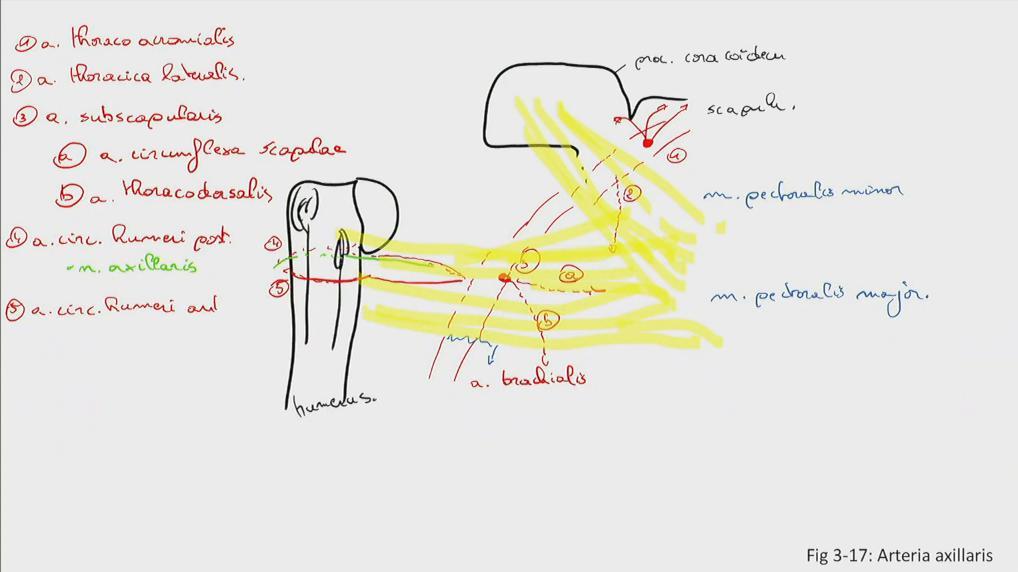

Fig 3.17: a. axillaris

-

scapula

-

humerus

tuberculum maius tuberculum minus crista tuberculi maioris crista tuberculi minoris collum chirurgicum

m pectoralis minor (geel) m pectoralis maior (geel) a thoracoacromialis a thoracica lateralis -

a subscapularis

a cx. scapulae a thoracodorsalis

a cx. humeri posterior (samen met n. axillaris door laterale okselpoort) a cx. humeri anterior a brachialis (vanaf onderrand m. pectoralis maior)

|